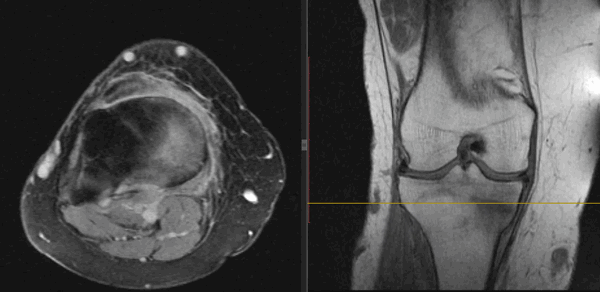

На Т2-ВИ в сагиттальной и корональной плоскостях определяется стресс-перелом дистальных отделов малоберцовой кости.

На Т2-fs-ВИ в сагиттальной плоскости определяется разрыва пяточного сухожилия.

(Слева) На фронтальной МРТ в режим STIR определяется диффузный сигнал высокой интенсивности в проксимальной половине полулунной кости. Этот локальный ушиб является результатом прямого удара о ладонь у подростка 13 лет.

(Справа) На фронтальной МРТ Т2ВИ FS определяется диффузный отек костного мозга в головчатой кости и в дистальном локтевом крае ладьевидной кости без различимого перелома. Этот молодой пациент упал на вытянутую руку.